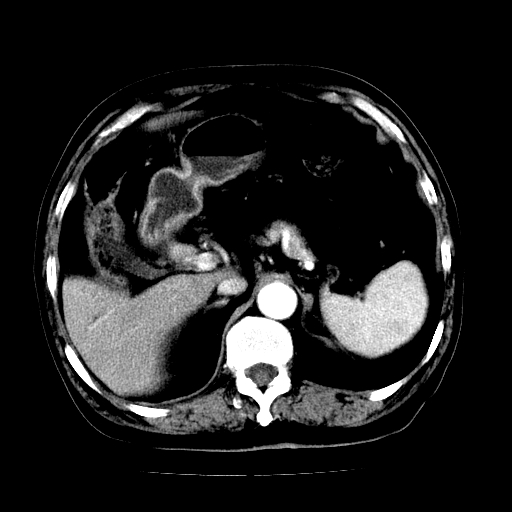

男,71岁,皮肤黄染四天。

肝内外胆管及胆总管上段扩张,考虑为梗阻所致,建议mrcp检查。

考虑胆总管癌并肝内外胆管扩张。

胆管癌并肝内外胆管扩张。

支持考虑胆总管癌并肝内外胆管扩张。 局部应薄扫。心包钙化。

胰腺上端胆总管内见软组织影,强化不明显,结合临床,还是考虑低位梗阻性黄疸,胆总管癌可能性大